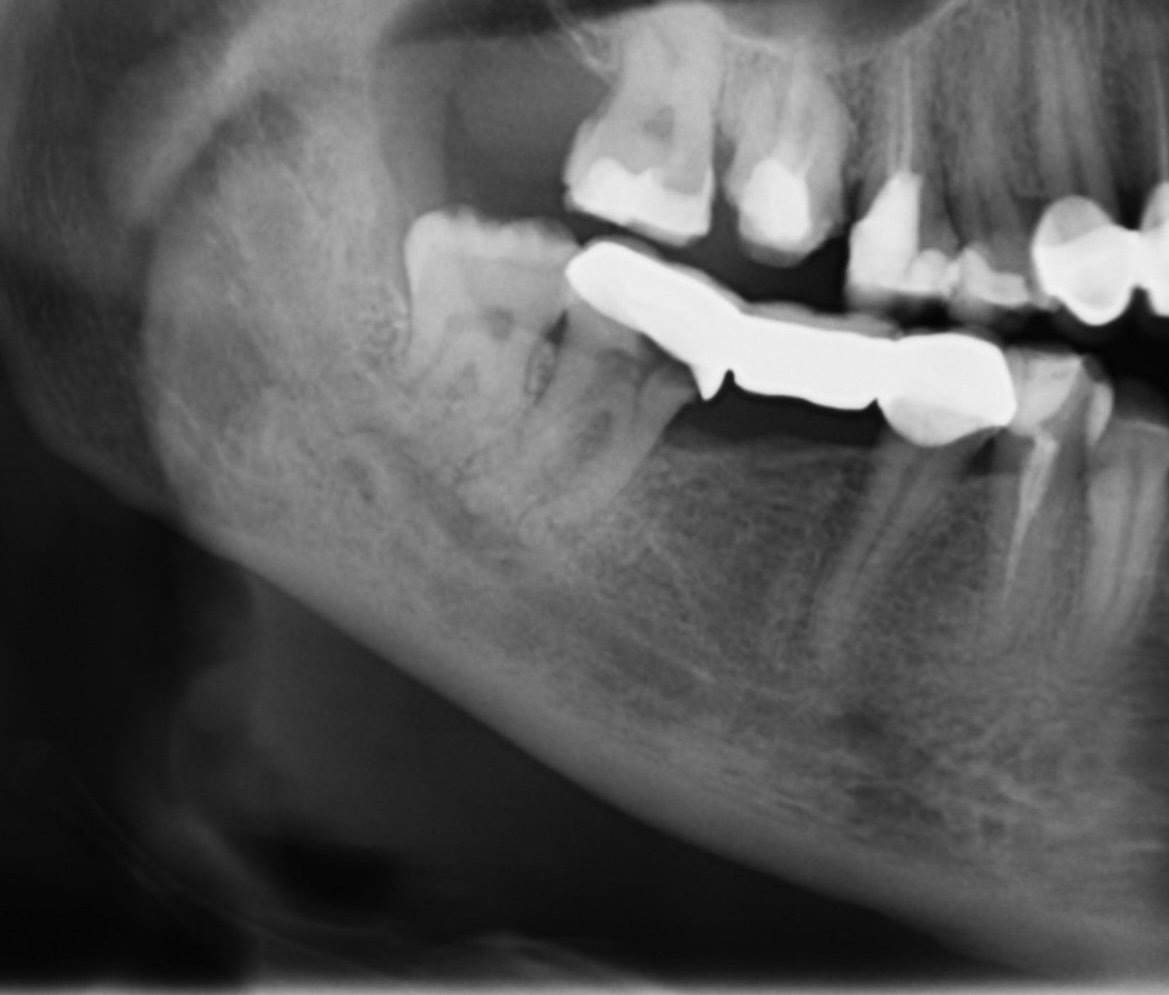

Имам мост на повече от 10 год. Усещах, че мърда и тази година реших да го сменя. Един от зъбите беше изгнил - черен. Първата панорамна снимка е от преди. Нямах болка.

Лекува го една зъболекарка, но предпочете да остана със стария мост, защото не е сигурна дали ще се оправи…

Днес направих нова панорамна (две седмици след нейното лечение) и друг зъболекар ми каза, че вече само в София при ендодонт, защото нищо не. Е направила, а има и скучен и инструмент.

Зъболекаря ми казва, че може и да не ме заболи. Моля за съвет, кое е най-добре в този случай. [/img]

Има счупен инструмент, не до край лекуван канал (стоматологът сигурно е срещнал затруднение с проходимостта) и според мен пропусната анатомия (канал). Т.е има доста работа по този зъб.

Според мен се насочете към специалист в тази област, зъбът в момента няма рентгенологични находки на възпаление, но предвид лечението не е изключено да Ви изненада в неподходящ момент.

Ако става въпрос за София мога да Ви насоча към специалисти, ако искате ми пишете на лично.